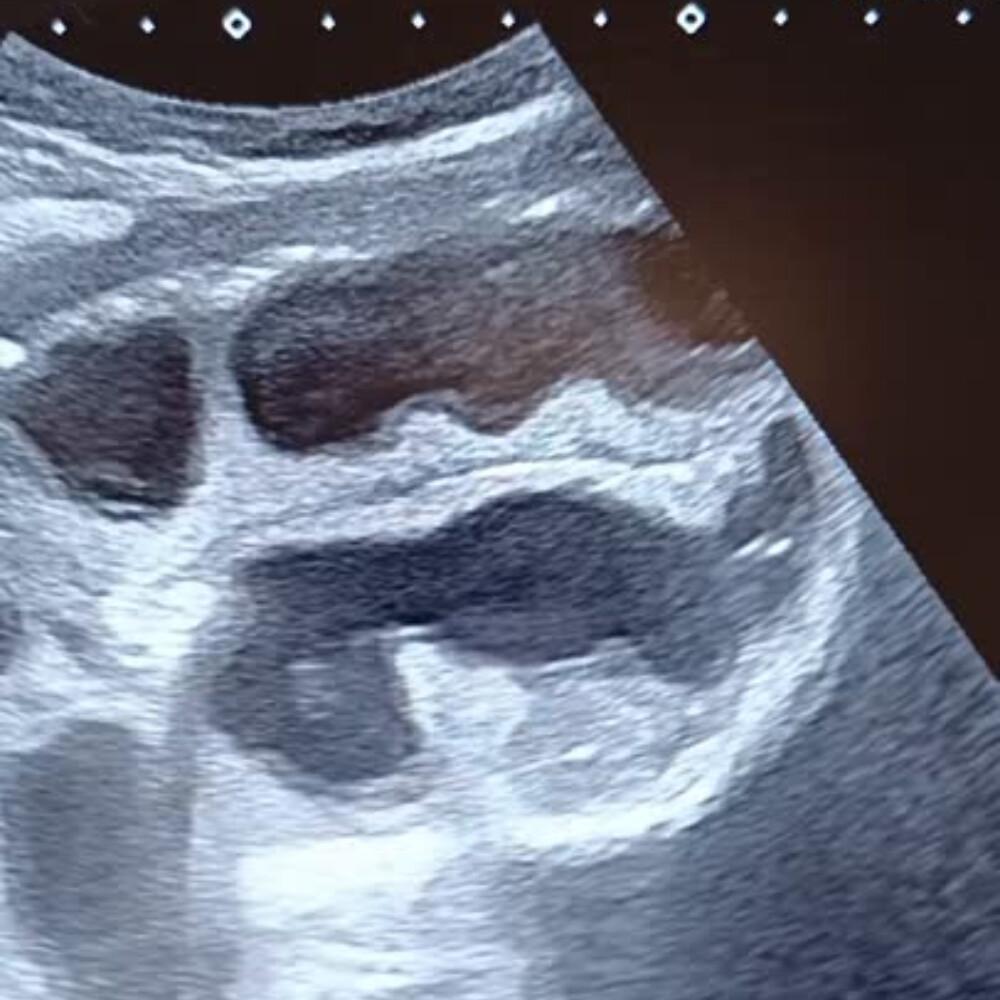

- Dilatation des anses grêles : diamètre > 25 mm (> 2,5 cm), contenu liquidien, paroi fine.

- Anses coliques : plus périphériques, contenu gazeux, haustrations visibles.